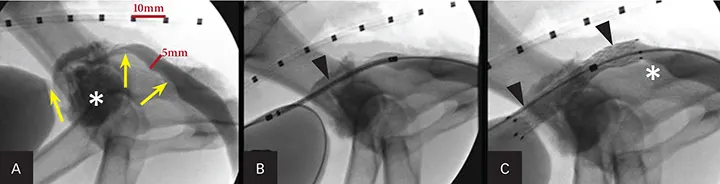

A reliable and safe alternative to establish urethral patency is placement of a self-expanding metallic stent by a transurethral approach with fluoroscopy (Figure 9). This outpatient procedure is associated with good-to-excellent palliative outcomes in more than 95% of cases. It has been successful in both dogs and cats; however, approximately 25% of patients will exhibit some urinary incontinence after stent placement.

Figure 9. Fluoroscopic images of a male dog during urethral stent placement for obstructive prostatic carcinoma (asterisk; A). Retrograde cystourethrography shows the obstructive lesion (arrows). A marker catheter is used to measure the urethral lumen diameter for stent sizing. A constrained urethral stent (arrowhead; B) is placed over a guide wire prior to deployment across the obstructive tumor. The deployed urethral stent (arrowheads; C) shows patency of the urethral lumen. There is still some tumor caudal to the stent (asterisk).